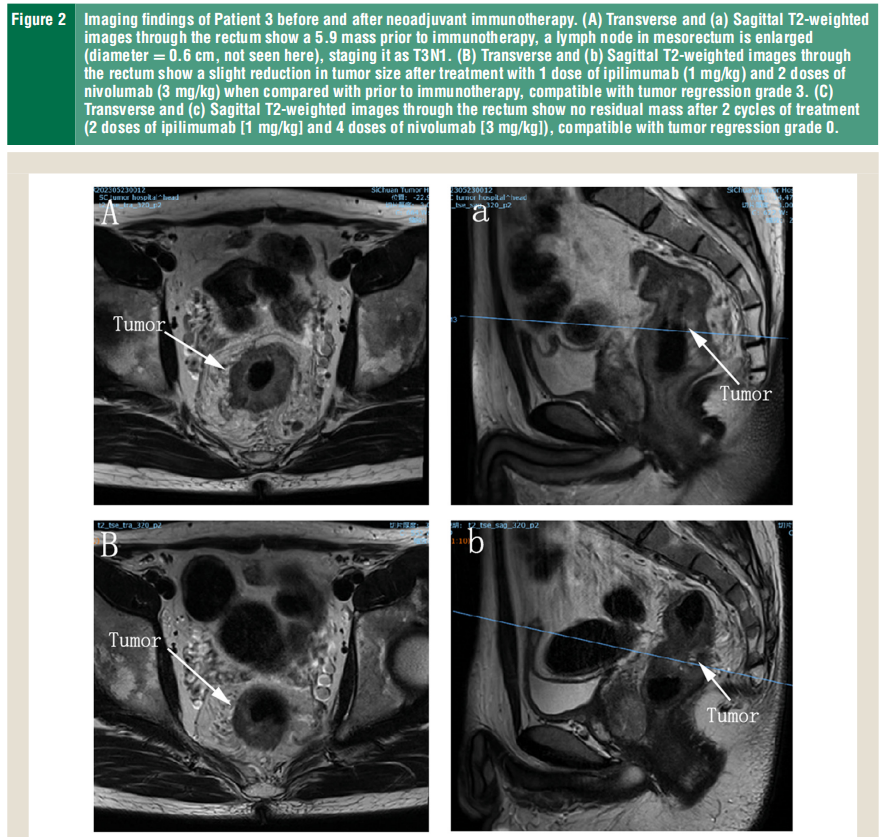

dmmrmsih晚期结直肠癌pcr达818新辅助伊匹木单抗纳武利尤单抗安全可行